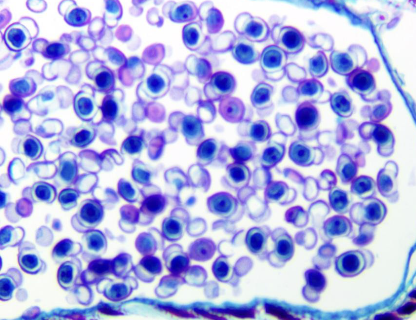

This organism falls within phylum:

Apicomplexa

Euglenozoa

Radiolaria

Chlorophyta

And what is the organism?

Phylum: Apicomplexa

Organism: Plasmodium vivax

What is the phylum Apicomplexa?

Plasmodium is a parasite living in blood of mammals and birds that causes malaria; carried by Anopheles mosquitoes.